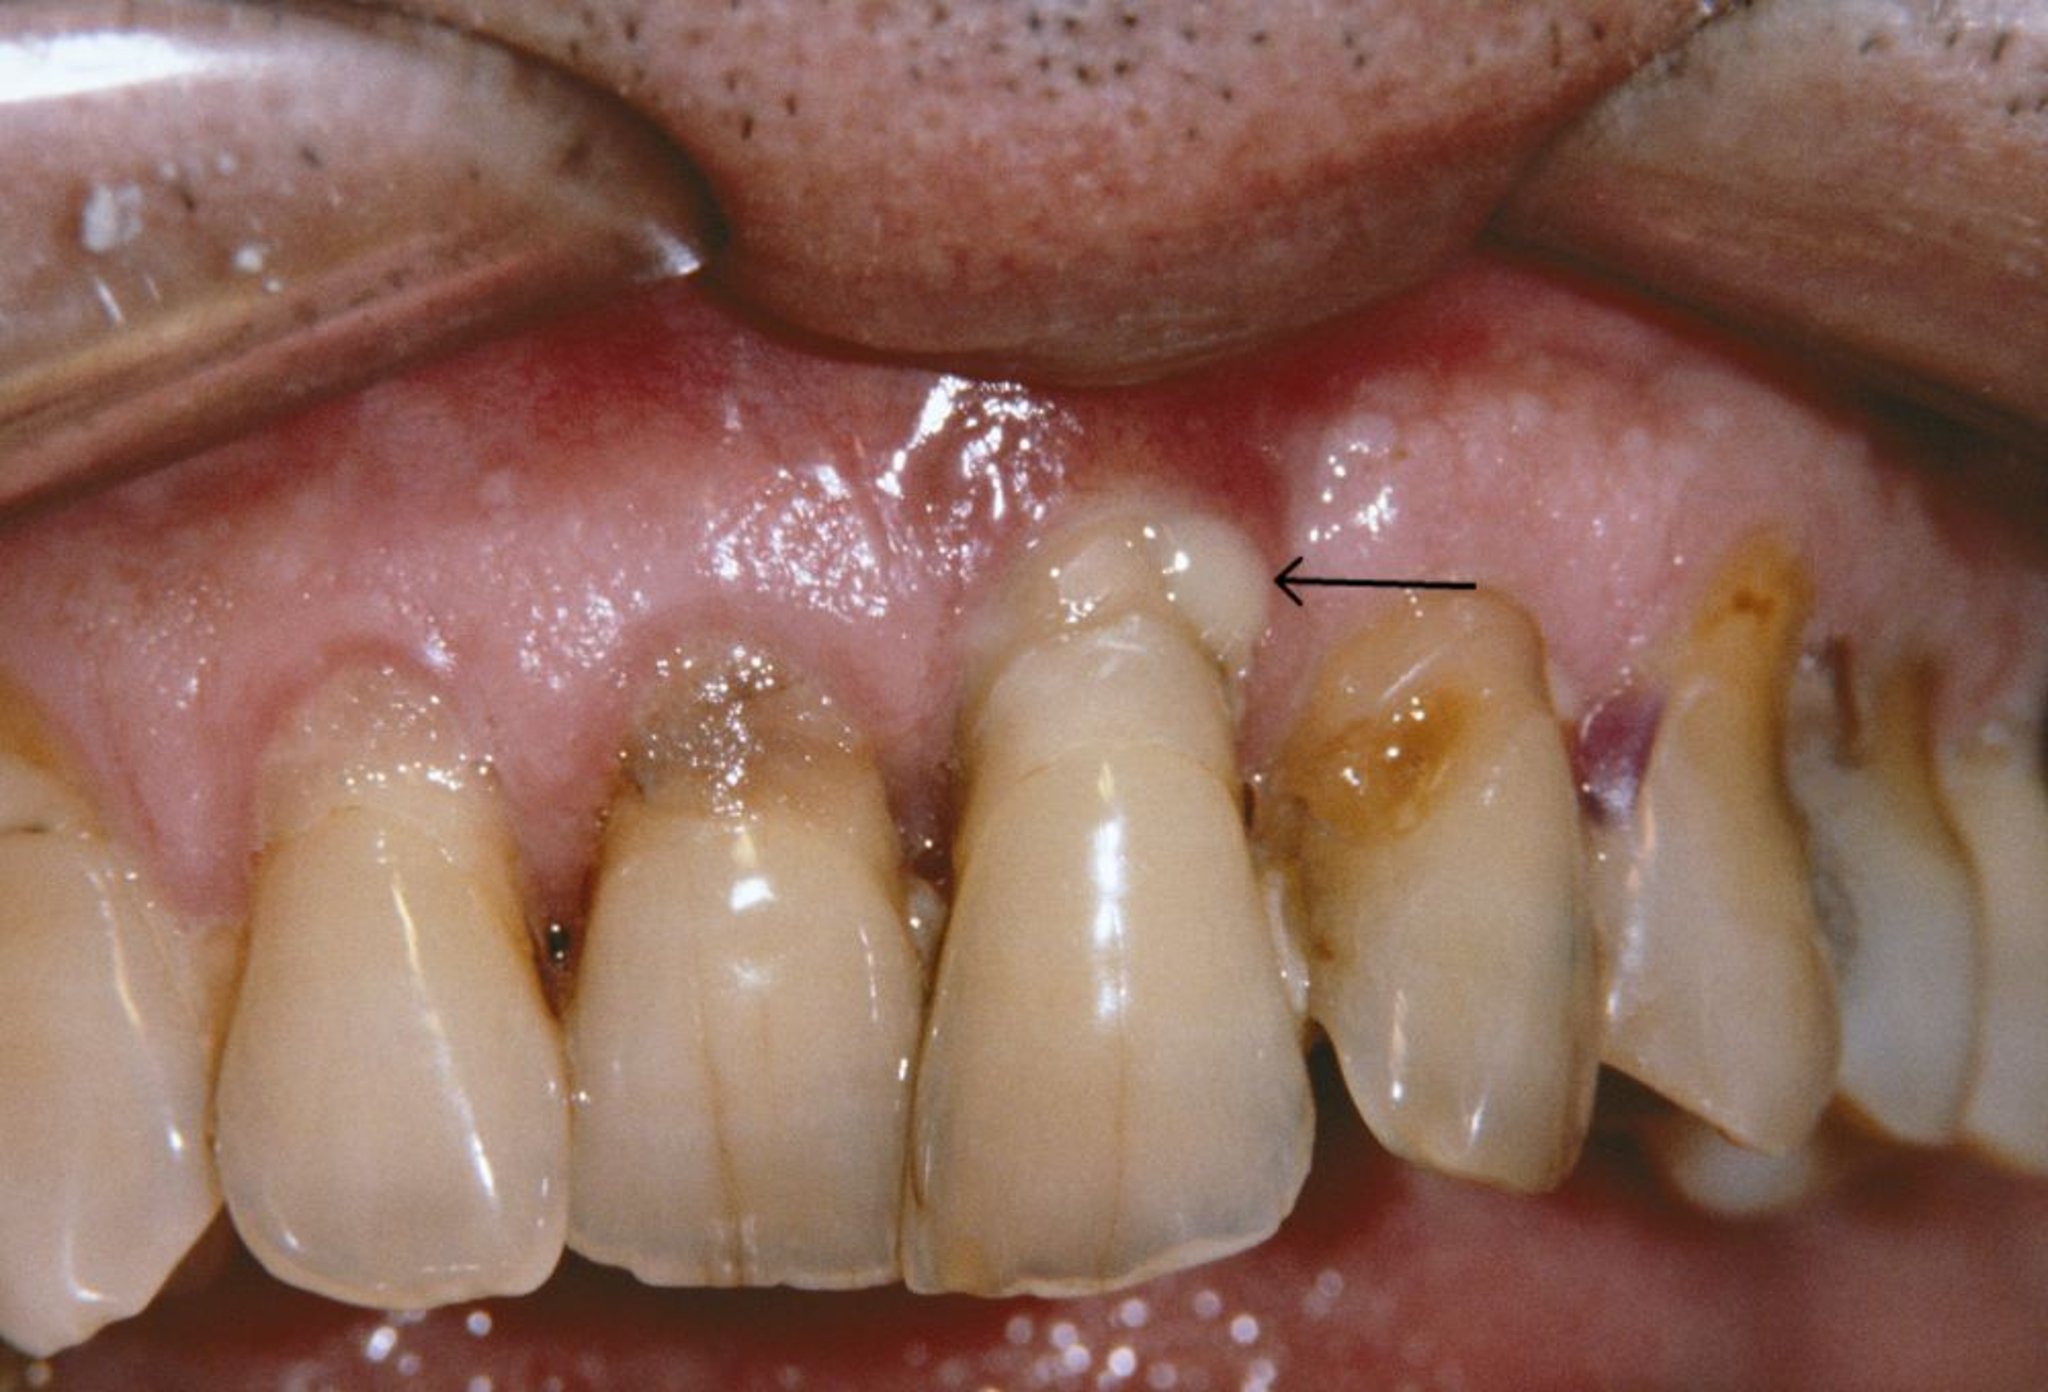

Questa foto mostra recessione gengivale e un ascesso parodontale (freccia) in una persona che ha parodontite.